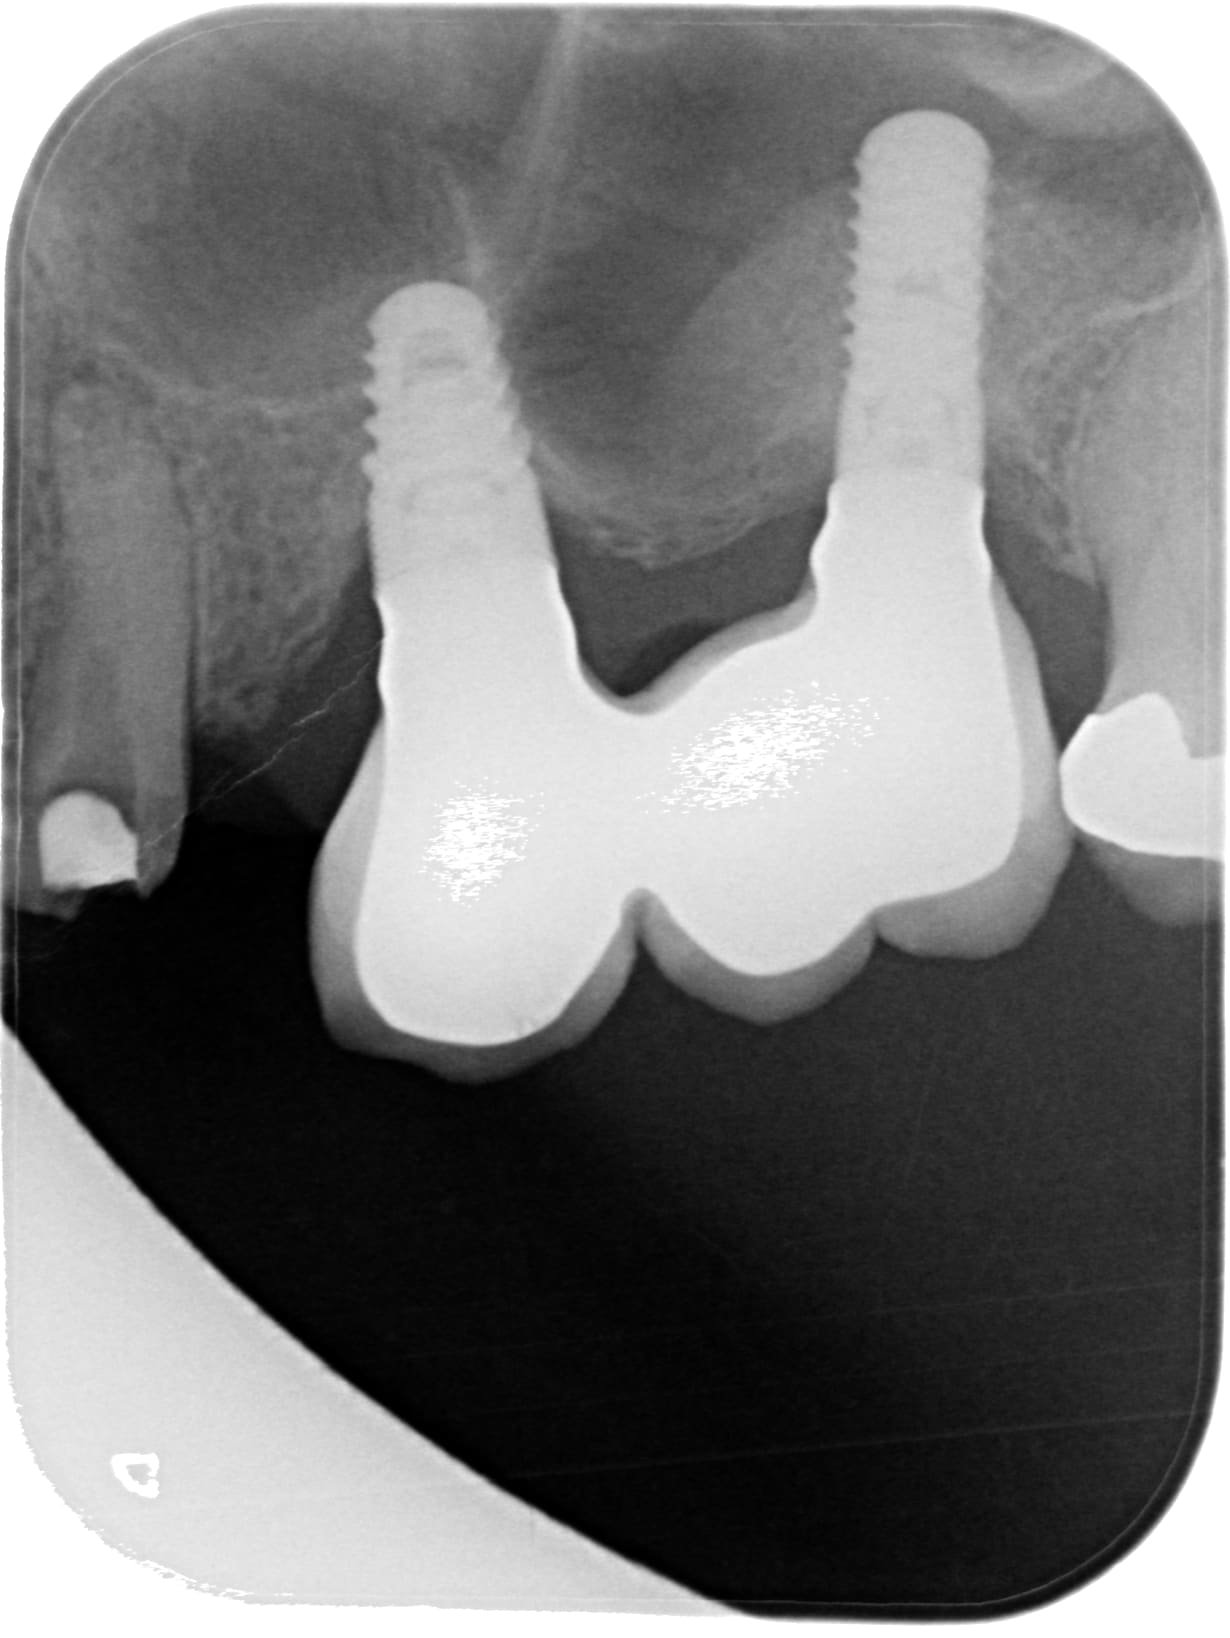

je vais démonter les couronnes transvissées solidaires 24 26 et faire un bridge en extension 23 à 26 car je n'ai pas assez d'épaisseur osseuse sur 23.

Je pense que les implants sont des idi et alphabio.